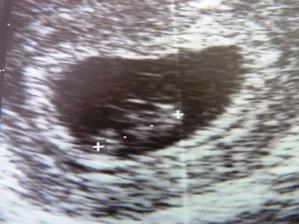

tak sa zda, ze uplne necakane sa zo mna stala tehulka 🙂 dufam ze vsetko dobre dopadne a narodi sa mi zdrave babo.

gratulujem.....takisto slabsie to mam aj ja a v utorok na sone mi to potvrdil doktor a hned mi zobral krv a aj tam isiel hormon hore....260.......takze to by sme mohli mat nejako narovnako, som si ratala a vysiel mi termin na 6.10.2011.....a pritom dva tyzdne riesili moju cystu, lebo som bola pripravena ist na druhe umele oplodnenie

je tam vidim aj ja:DDDD